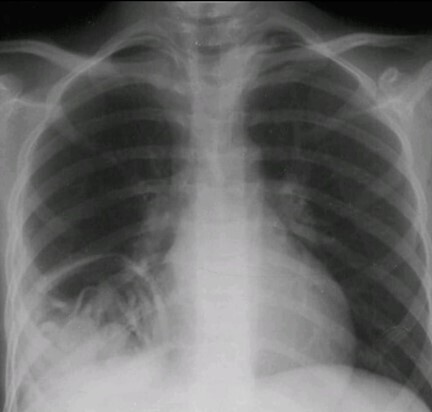

Une radiographie thoracique est réalisée.

Il s’agit d’un kyste hydatique pulmonaire rompu. Voir explications ci-dessous.

• L’aspect radiologique typique avec niveau liquide-gaz et membranes flottantes correspond au « signe du nénuphar » (ou water lily sign), caractéristique d’un kyste hydatique pulmonaire rompu.

– Le niveau liquide-gaz dans une cavité arrondie est classique, mais non spécifique ;

– Ce qui oriente fortement ici est la présence de membranes flottantes à l’intérieur du kyste, dessinant le « signe du nénuphar » (ou water lily sign), considéré comme quasi pathognomonique d’un kyste hydatique rompu.